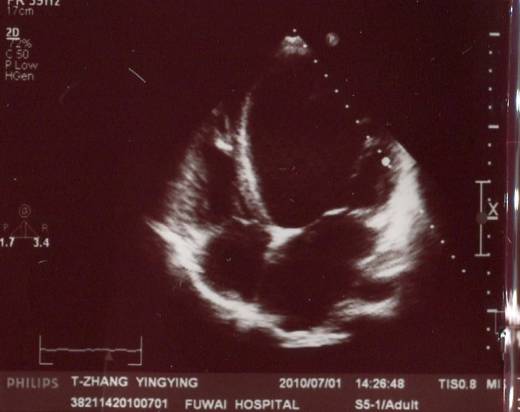

超声心动图

►超声心动:LA 36mm,LV 86mm,LVEF 20%,RV 24mm

►左房轻度增大,左室明显扩大成球形,左室壁弥漫性运动减弱,右房室不大,二尖瓣中大量返流